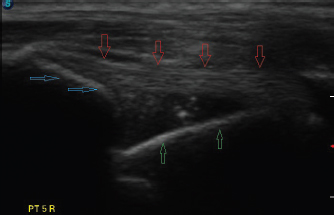

The dog was placed in lateral recumbency with the affected limb uppermost. Hair was clipped to expose the humeral tubercle and intertubercular groove. Using a 12 mHz linear probe, the biceps tendon was visualized longitudinally from the musculotendinous junction within the groove, proximally to the tendinous origin on the supraglenoid tubercle (Fig. 3). Any abnormalities and the approximate tendon size were noted. The biceps tendon was then positioned under tension by placing the shoulder in flexion with concurrent elbow extension, so that the forelimb lay roughly parallel to the topline. With the limb in this position, the appearance of the biceps tendon as it spanned the glenohumeral joint was noted, and images were saved to the ultrasound’s hard drive.

Fig. 3. Longitudinal ultrasound image of an intact biceps tendon (red arrows), supraglenoid tubercle (blue arrows), and proximal humerus (green arrows).